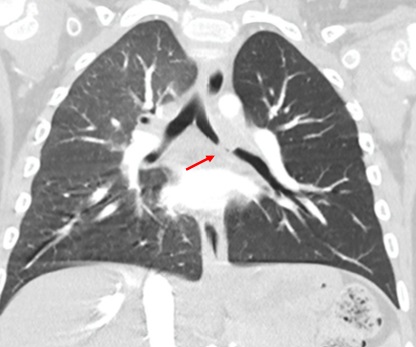

Niña de 2 años valorada en consulta por tos seca nocturna y escucha de sibilancias de una semana de evolución, sin fiebre asociada. Diagnóstico inicial de broncoespasmo en medio hospitalario, tratado con broncodilatadores inhalados. Ante la falta de mejoría se revisa en el centro de salud y se aprecia en la auscultación asimetría con hipoventilación del campo pulmonar izquierdo, por lo que se deriva a urgencias, donde la radiografía se informa como: “asimetría entre ambos campos pulmonares con aumento de la radiolucencia y del volumen del pulmón izquierdo compatible con atrapamiento aéreo” (Figura 1). Ante la sospecha de cuerpo extraño bronquial, se programa un TAC, que informa la presencia de una lesión endobronquial dependiente de la pared posterior del tercio medio del bronquio principal izquierdo (Figura 2). El TAC describe una lesión redondeada y de aspecto polipoide con obstrucción prácticamente completa de la luz bronquial. Se realiza broncoscopia con toma de biopsias y resultado anatomopatológico compatible con granuloma, por lo que se programa exéresis de la lesión vía endoscópica. El estudio anatomopatológico confirma inflamación crónica granulomatosa necrotizante. Baciloscopia y cultivo de micobacterias de lavado broncoalveolar: Mycobacterium avium. Ante este resultado, se inició un tratamiento combinado con rifampicina, etambutol y azitromicina, sin toxicidad y con buena adherencia. A nivel clínico, tras la resección hay una mejoría clínica respiratoria sin complicaciones hasta los cinco meses, cuando, por la objetivación de cianosis de esfuerzo por los padres, se solicita radiografía en la que se aprecia un inicio de consolidación en lóbulo inferior izquierdo, prescribiendo tratamiento antibiótico con amoxicilina-clavulánico. Se programaron broncoscopia y TAC que descartaron recidiva. Se recogieron muestras para un cultivo convencional y micobacterias, siendo negativas. Se solicitó a su vez panel de virus respiratorios, con resultado positivo en rhinovirus y enterovirus.